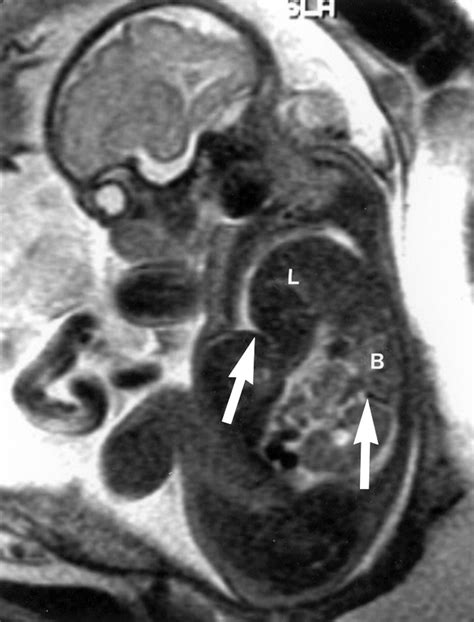

In many modern medical settings, CDH is often identified before birth during routine prenatal ultrasounds. If an anomaly is suspected, doctors may utilize fetal MRI or advanced echocardiograms to assess the severity of lung development and heart positioning.

To fully grasp what is CDH, one must understand how it physically alters a newborn's anatomy. The diaphragm is essential for normal breathing. When a hole exists in this muscle, the vacuum pressure changes within the thoracic cavity. As the abdominal organs migrate into the chest, they compress the developing lungs, hindering the branching of the airways and the development of blood vessels.

The severity of CDH is largely determined by the timing of the defect during gestation and the specific organs that migrate into the chest. In many cases, the heart may also be pushed out of its normal position, which can further impact circulatory function at birth. This combination of underdeveloped lungs and potential circulatory strain is why babies born with CDH require specialized neonatal care immediately upon delivery.

When expectant parents hear the term Congenital Diaphragmatic Hernia, it often triggers immediate confusion and anxiety. What is CDH, and how does it affect a developing fetus? At its core, Congenital Diaphragmatic Hernia (CDH) is a serious birth defect that occurs when the diaphragm—the thin, dome-shaped muscle that separates the chest cavity from the abdomen—fails to form correctly during fetal development. This failure leaves an abnormal opening, allowing abdominal organs such as the stomach, intestines, or liver to push upward into the chest cavity. Because these organs occupy space meant for the developing lungs, the lungs often fail to grow to their full size, leading to a condition known as pulmonary hypoplasia. Understanding this condition is the first step for parents navigating a complex medical journey.